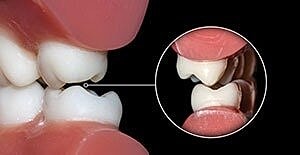

Damaged or disfigured teeth that do not need a dental crown can be restored with inlays or onlays. An inlay fills cracks or divots between the cusps of teeth. Onlays or “partial crowns” cover a portion of the tooth to restore height or shape.